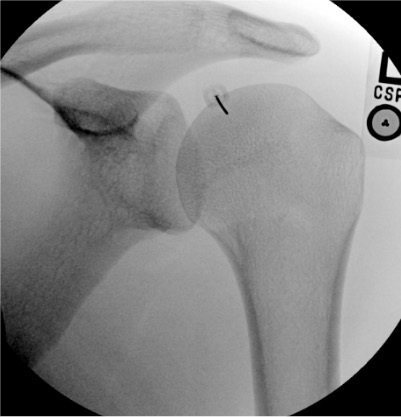

Shoulder

Needle placementPost-injection